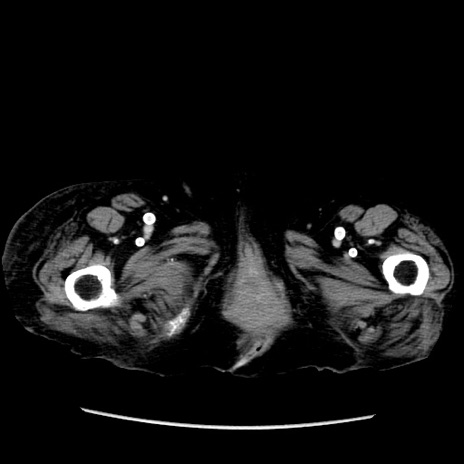

症例14(横断像)

【症例】 90歳代女性

【主訴】 腹痛・嘔吐

【現病歴】今朝から左側腹部痛を認めた。 経過観察していたが、嘔吐を認めたため来院。

【既往歴】 子宮癌術後

【身体所見】 意識清明、BP 127/54mmHg、P 98bpm Sp02 95%(RA)、BT 35.8°C、腹部平坦・軟腸ぜん動音聴取良好、右下腹部圧痛(+) 反跳痛なし

【データ】WBC 9800、CRP 0.46